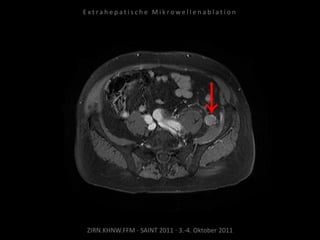

Kontrolle:

MRT 18.05.2010

MRT 01.07.2010

Das abladierte Tumorrezidiv zeigt keine

Vitalität. Jedoch neu aufgetretene

Tumormanifestation kranial im Bereich der

angrenzenden Samenbläschen.

Ablation des entsprechenden Areals

am 06.07.2010:

2 Nadelpositionen.

Erneut mit Kühlung von Harnleiter,

Harnblase und Rektum.